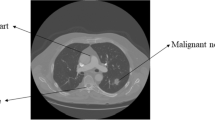

Immunohistochemistry is widely used in clinical pathology analysis and diagnosis, the target regions segmentation is the key procedure and always provides support for many qualitative and quantitative analyses on digitized immunohistochemical image. In lung tissue immunohistochemistry applications, the target region needs to be extracted out of the whole image firstly. Most existing methods based on color cannot fulfill the extraction of antibody region. Thus, there is a need of effective extraction method. Methods: According to the features of target region in images to be processed, this paper presents a solution framework based on artificial neural network (ANN). Results: Six effective features of the candidate regions are analyzed and extracted as the inputs of the ANN; three-layers back propagation neural network with six inputs and one output is constructed, and ANN’s parameters are trained by the learning image set. By the trained ANN, target region core are obtained and then expanded to the whole target region through conditional expansion. Conclusion: Through testing the framework by testing image set and comparing with the main existing methods, it can be concluded that the proposed framework can remove non-target regions and extract the target regions well, while the contrast methods cannot remove all the non-target regions. Significance: The method presented in this paper has practical and potential significance to realize automated and quantitative tissue immunohistochemical image analysis.

Fan, D., Wei, L. & Cao, M. Extraction of target region in lung immunohistochemical image based on artificial neural network. Multimed Tools Appl 75, 12227–12244 (2016). https://doi.org/10.1007/s11042-016-3459-2